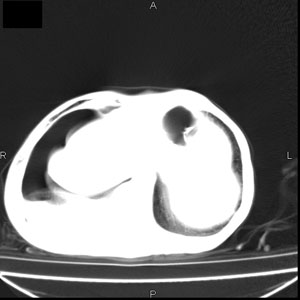

患者男,77岁,于3日前从树上摔下,头部查ct示蛛血,硬膜下出血,上腹部ct未见明显异常,右侧胸腔积液,左侧如常。肺部拍片示右侧肋骨多发骨折住院后今日来查肺部ct,我看到的是1。右侧胸腔血气胸并右肺上叶,中叶压缩性肺不张,2。右肺下叶肺挫伤并多发肋骨骨折,肌内及皮下积气3。左侧少量胸腔积液,我想请教的是3天前左侧胸腔里没有积液今天怎么出现了呢,是什么原因呢?请讨论。

有肺挫裂伤,有渗出,

回复楼主   左侧液气胸,液体来源1、肯定有血液成分,多少不一定。2、胸膜腔渗液,由于肺压缩、活动度下降,肯定胸膜吸收有问题,导致积液增多。

因为3天前病人刚摔的时候,左侧胸腔受伤不严重,故而当时没有胸腔积液,但病人受到这么大的伤害,胸膜腔内的液体动态平衡肯定会受到影响,所以过一段时间后才出现胸腔积液。

1、外伤出血需要一定的时间

2、气胸存在时间长了,产生的胸膜渗液

考虑外伤性迟发性胸腔积液。